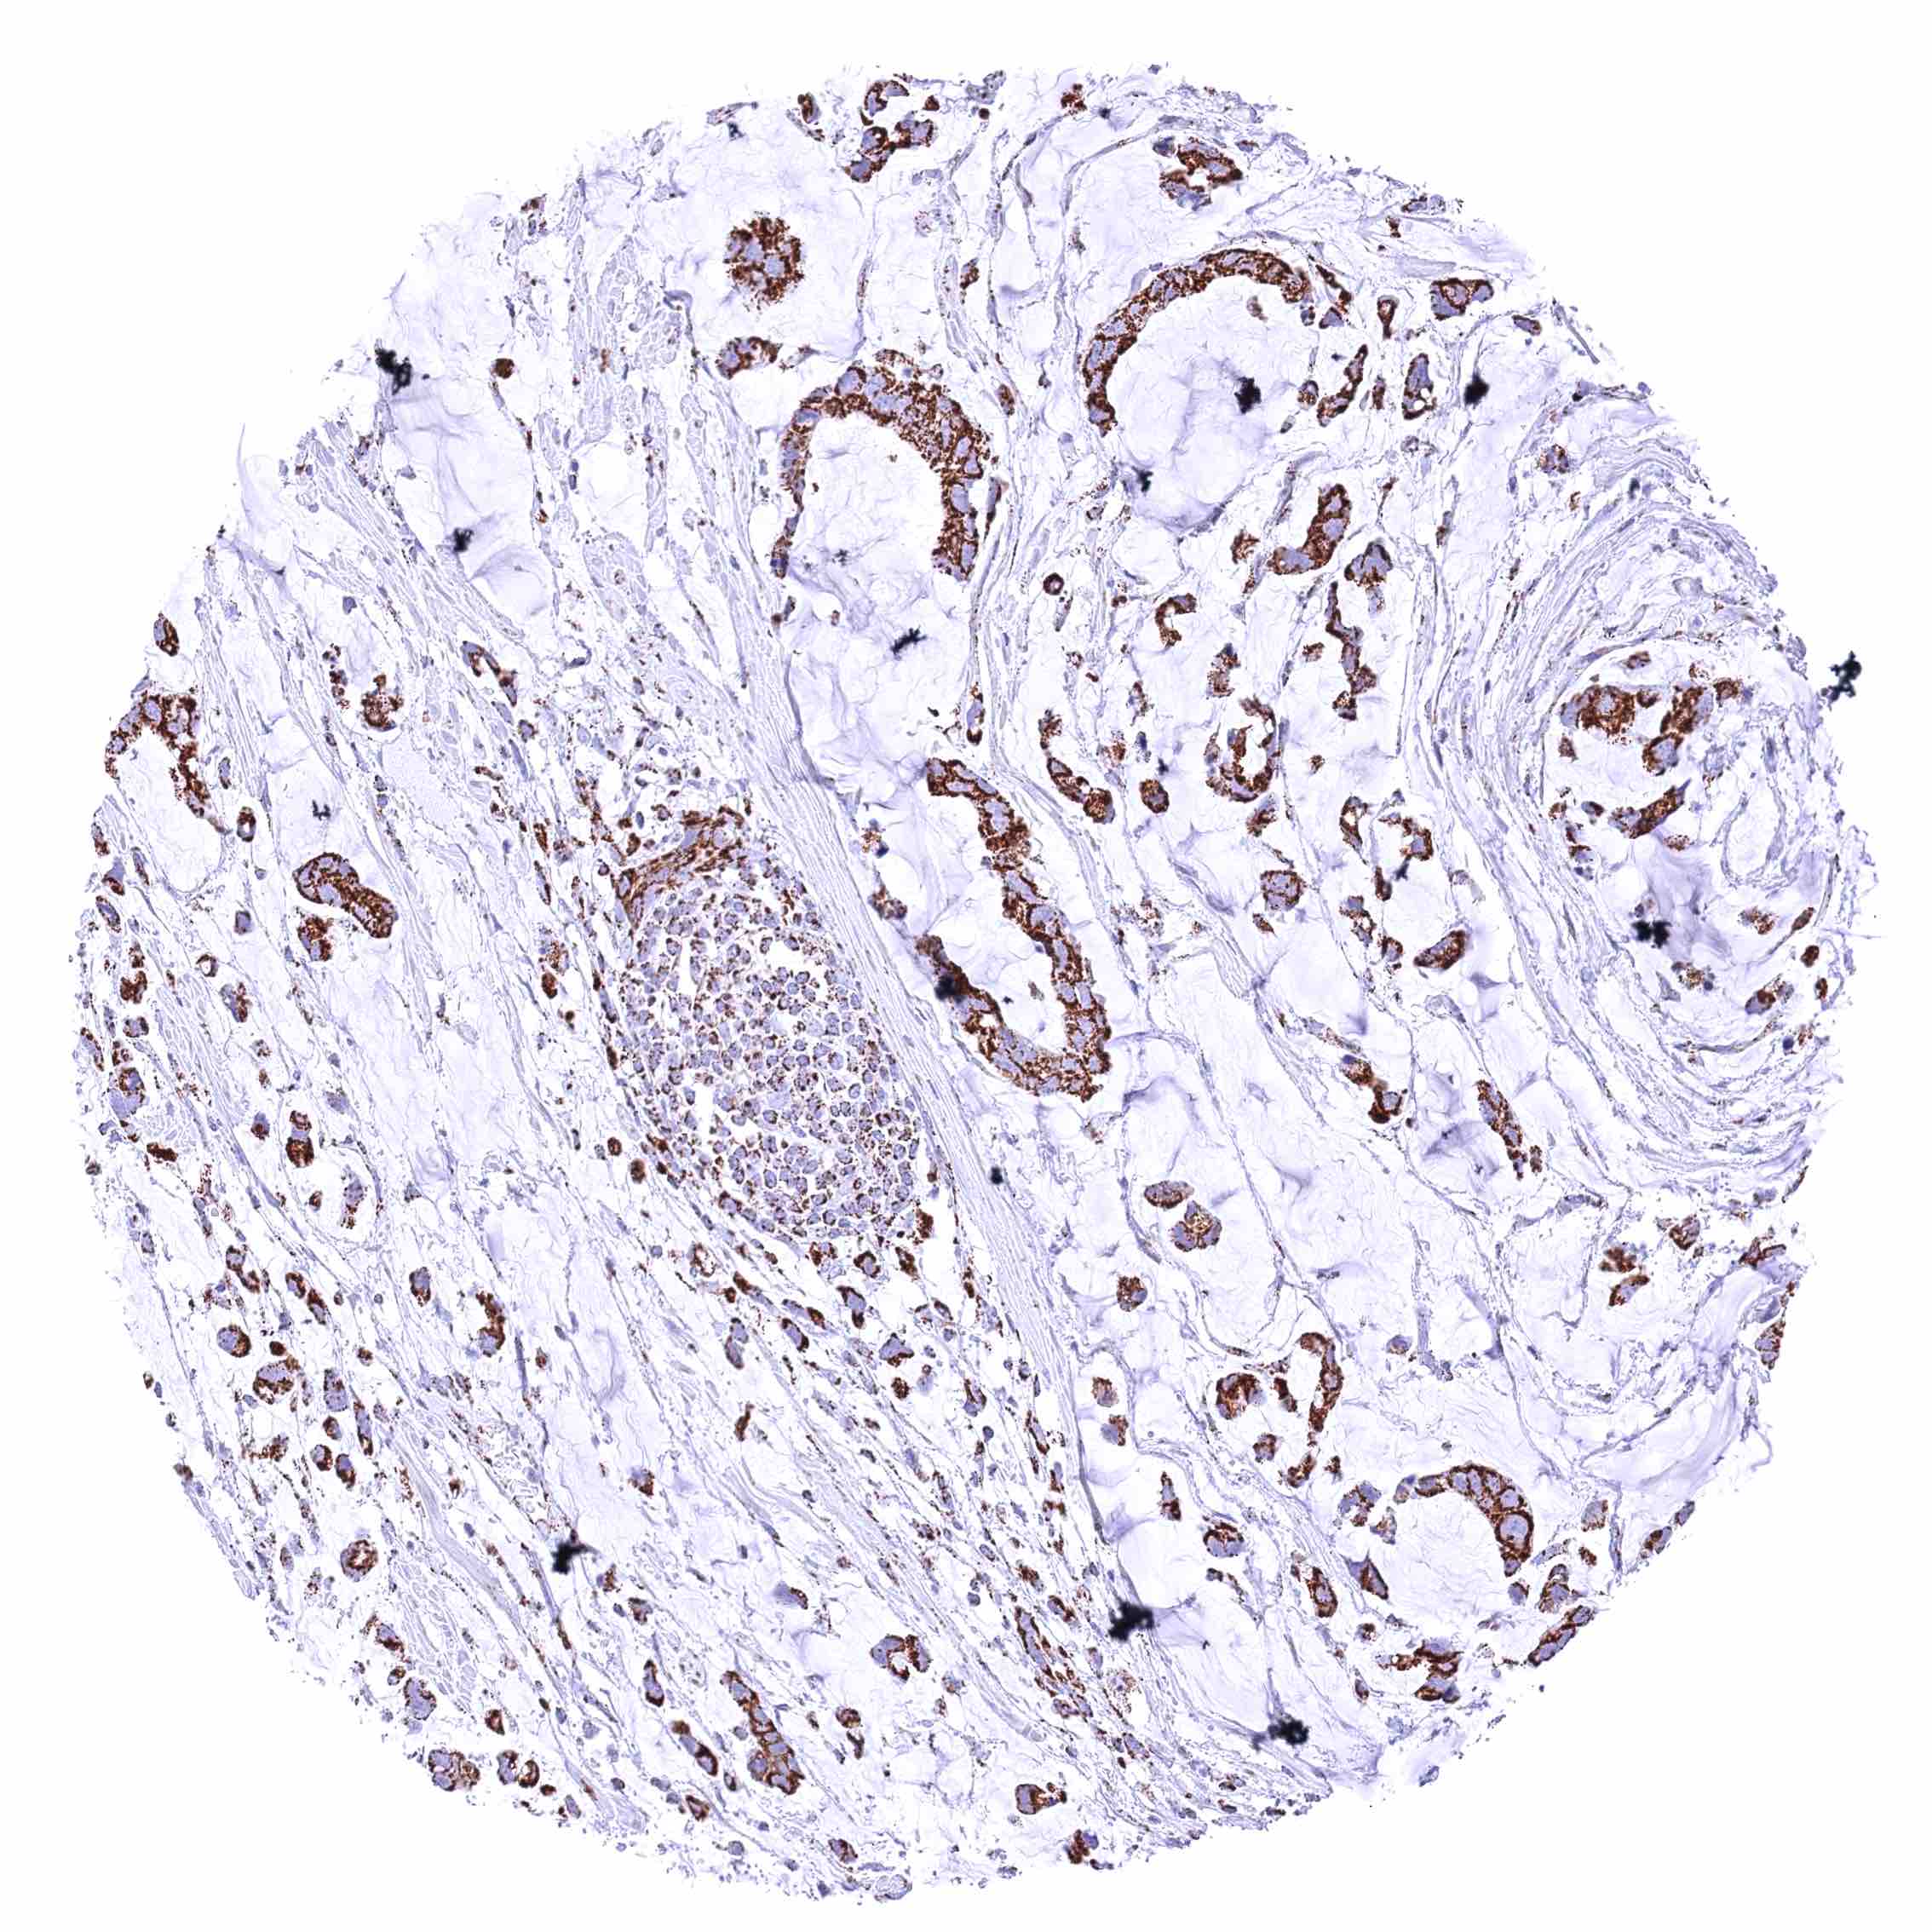

Prostate – Adenocarcinoma (Gleason 3+3=6) with moderate cytoplasmic ATP5J staining of tumor cells.